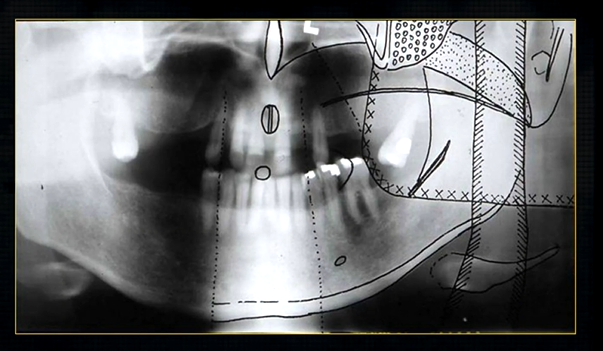

dental radiographic images are 2D representations of the 3D teeth and bones of the skull

it is important that you are aware of the whole skull but particularly the maxilla and the mandible

resultant radiographs are always 2d demonstrations of a 3d object - all structures, internal and external will be superimposed on one another

how the anatomy is presented geometrically is dependent on the relative positions of the patient, image receptor and the X ray beam

to see both jaws, a panoramic radiograph can be taken

this creates a complicated radiograph with several types of shadows superimposed on top of each other - image shows why the cervical spine appears on both sides of the image - anatomical structures are severely distorted

real hard tissue shadows

real hard tissue shadows of nasal septum, hard palate, maxilla, zygoma, mandible and the hyoid

real soft tissue shadows

real soft tissue shadows of the soft palate, ear lobe and the dorsum of the tongue

real equipment shadows

bite peg and the plastic head support

ghost hard tissue shadows

mandible from the opposite side

cervical spine

shadows of the air space - between the tongue and the roof of the mouth